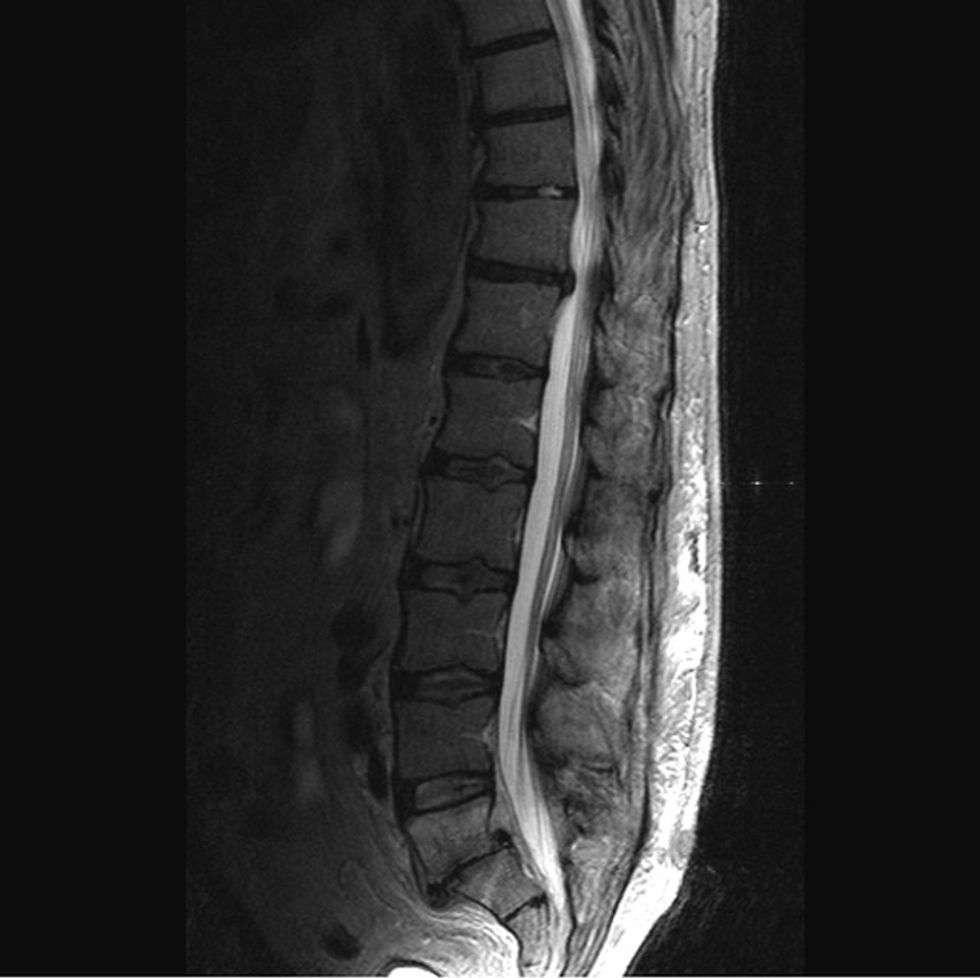

Ct dhe MRI në raste të posaçme kur dyshojmë që kemi të bëjmë edhe me shtypje të rrënjëve nervore (radikulare)

Spondylolisthesis definohet si rrëshqitje e përparme apo e pasme e unazës krahasuar me tjetrën nën të, me apo pa instabilitet spinal.

Rëntgen standard në dy drejtime, rtg në dinamikë - përkulje nga përpara apo nga prapa dhe anash.